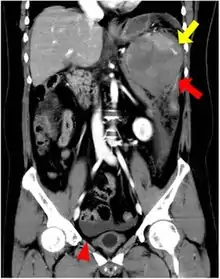

| CT scan of an accessory spleen (in center of image) between the spleen and left kidney. | |

If splenectomy is performed for conditions in which blood cells are sequestered in the spleen, failure to remove accessory spleens may result in the failure of the condition to resolve.[1] During medical imaging, accessory spleens may be confused for enlarged lymph nodes or neoplastic growth in the tail of the pancreas,[5] gastrointestinal tract, adrenal glands or gonads.[2]